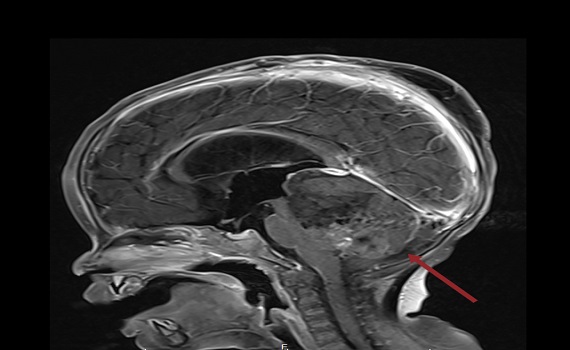

臺北醫學大學臺北癌症中心兒童腦瘤團隊召集人黃棣棟教授表示,ATRT是非常罕見的惡性腦瘤,通常好發三歲以下幼童,臺灣平均兩年約有兩例,而臺北癌症中心收治的患者於2022年8月時確診時僅9個月大,當時腫瘤幾乎佔滿病童的後顱窩的中央部分,由於難度高,必須分兩次手術切除,所幸手術順利,之後再搭配腫瘤部位質子及藥物治療,讓該名病童恢復良好。

臺北醫學大學附設醫院放射腫瘤科主任李欣倫醫師指出,幼兒的腦部在0至3歲間發展最為迅速,接受放射治療的年紀越小或照射範圍越大,5年內智商下降幅度越大,甚至身高、視力及內分泌系統都可能受到損害,所以過去未滿三歲病童極少接受放射治療,而質子治療的特性即可有效精準打擊腫瘤部位,高劑量消滅腫瘤,同時閃避眼睛、正常腦部等健康器官組織。

黃棣棟強調,ATRT患者過去接受全腦脊髓放射治療時很容易照射到脊椎骨,影響幼童的生長及造血系統,患者的存活率約逾4成,但不做放射治療的腫瘤控制更差,而透過質子治療有機會排除這些風險,對周邊組織的保護效果好很多,而觀察該名幼童在十個月大時接受腫瘤質子治療,為全球質子治療幼童的罕見案例,目前恢復狀況不錯,令人振奮。